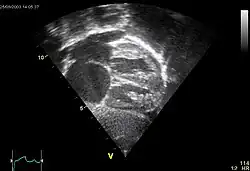

Echocardiography

In transthoracic echocardiography, an atrial septal defect may be seen on color flow imaging as a jet of blood from the left atrium to the right atrium.

If agitated saline is injected into a peripheral vein during echocardiography, small air bubbles can be seen on echocardiographic imaging. Bubbles traveling across an ASD may be seen either at rest or during a cough. (Bubbles only flow from right atrium to left atrium if the right atrial pressure is greater than left atrial). Because better visualization of the atria is achieved with transesophageal echocardiography, this test may be performed in individuals with a suspected ASD which is not visualized on transthoracic imaging. Newer techniques to visualize these defects involve intracardiac imaging with special catheters typically placed in the venous system and advanced to the level of the heart. This type of imaging is becoming more common and involves only mild sedation for the patient typically.

If the individual has adequate echocardiographic windows, use of the echocardiogram to measure the cardiac output of the left ventricle and the right ventricle independently is possible. In this way, the shunt fraction can be estimated using echocardiography.

- "UOTW #54 - Ultrasound of the Week". Ultrasound of the Week. 30 July 2015. Retrieved 27 May 2017.